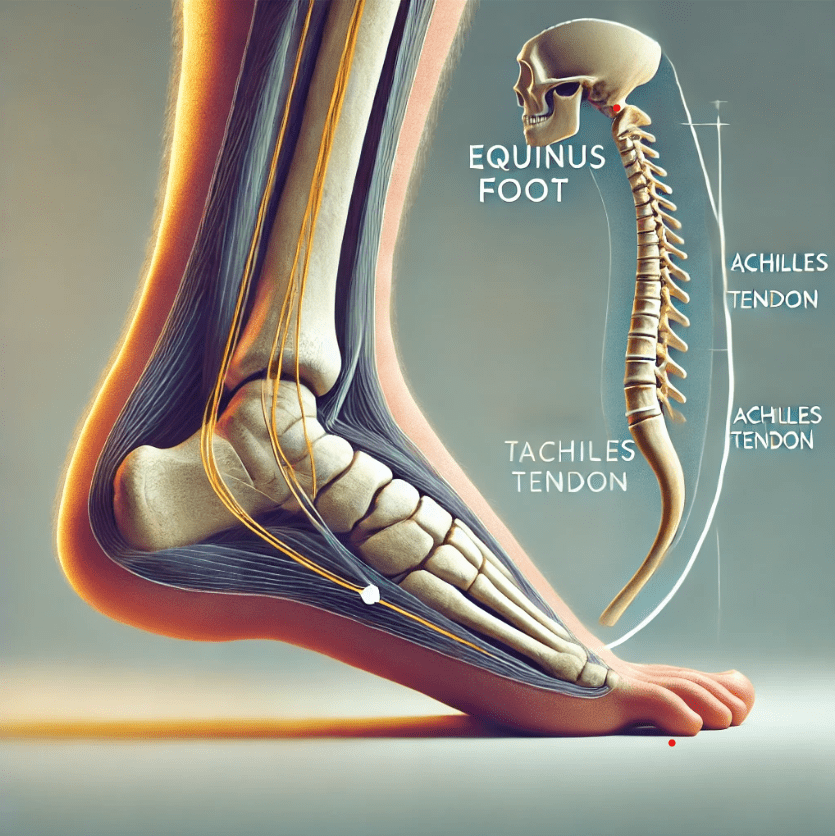

Periostitis tibial y tendón de Aquiles en corredores: importancia de la biomecánica

La periostitis tibial y las lesiones en el tendón de Aquiles son dos de los problemas más frecuentes en corredores de todos los niveles. Factores biomecánicos, como una técnica de carrera deficiente o desequilibrios musculares, pueden predisponer a sufrir estas patologías. La correcta evaluación y tratamiento desde la fisioterapia especializada permite no solo recuperar la […]